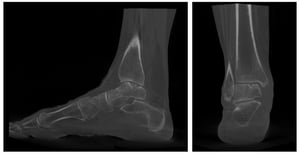

La scelta tra questi approcci non è discrezionale. Per definire la soluzione migliore è necessario fare una valutazione specialistica con il chirurgo che, sulla base della clinica e degli esami (Rx in carico, RMN e TAC), valuterà la strategia a seconda del tipo di lesione. Dimensione, profondità e localizzazione della lesione, oltre all’età del paziente, sono i parametri che orientano ogni decisione.

La TAC in carico, infatti, offre la possibilità di ottenere una misura affidabile della lesione, ma anche di andarne a misurare la reale forma, grazie a strumenti associati a intelligenza artificiale. Apprezzare la forma della lesione permette di essere ancora più precisi e di scegliere la tecnica che permetta la ricostruzione anatomica più efficace associando tecniche diverse di rigenerazione in base al caso.

L'iter strumentale raccomandato prevede tre esami distinti, ciascuno con un ruolo specifico.

Prima di tutto, la risonanza magnetica per studiare la biologia della lesione e accertare l'entità dell'edema osseo.

Poi la TAC, per comprendere le reali dimensioni della lesione, che la risonanza spesso sovrastima.

Infine la radiografia eseguita in carico, per identificare eventuali deviazioni assiali del retropiede o della caviglia che potrebbero sovraccaricare l'area lesionata e compromettere il risultato della terapia.

Questi tre esami non sono intercambiabili. Forniscono informazioni complementari e vanno interpretati insieme dallo specialista per definire la strategia terapeutica più adatta. La diagnosi definitiva spesso avviene a distanza dall'evento acuto, perché la risonanza magnetica è un esame di secondo livello, da pianificare ad almeno 20 giorni dopo un evento distorsivo.